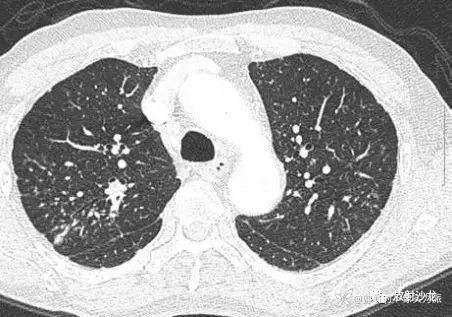

患者开始口服泼尼松治疗,初始剂量为0.5mg·kg-1·d-1,治疗1wk后,患者的呼吸系统症状迅速缓解,肺部多发结节也得到明显吸收(图5) ;2wk后泼尼松剂量减至0.25mg·kg-1·d-1。现该患者在定期随访中。

图5 2wk治疗后,复查CT示多发结节得到明显吸收